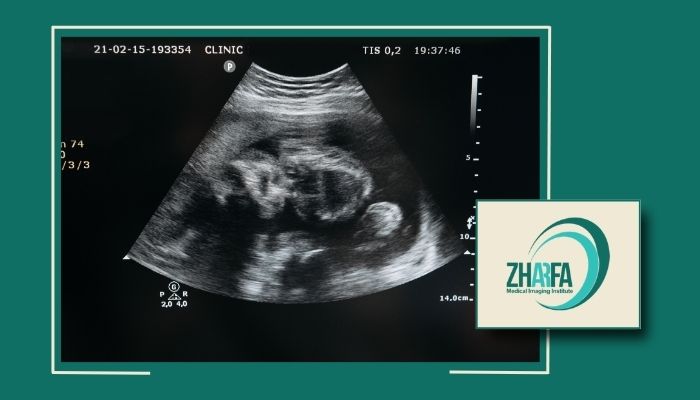

سونوگرافی آنومالی در پیروزی و شرق تهران برای تشخیص دقیق مشکلات جنینی

اهمیت سونوگرافی غربالگری ناهنجاریهای جنین

زمان مناسب سونوگرافی آناتومیک جنین

تفاوت سونوگرافی آنومالی با سایر سونوگرافیها

محتوای تصویربرداری: در این تست ساختارهای داخلی جنین مانند قلب، مغز و ستون فقرات بررسی میشوند ولی در تستهای چند بعدی تصاویر سه بعدی از جنین ایجاد میکنند و بیشتر برای مشاهده حرکتها و ویژگیهای صورت جنین استفاده میشوند.